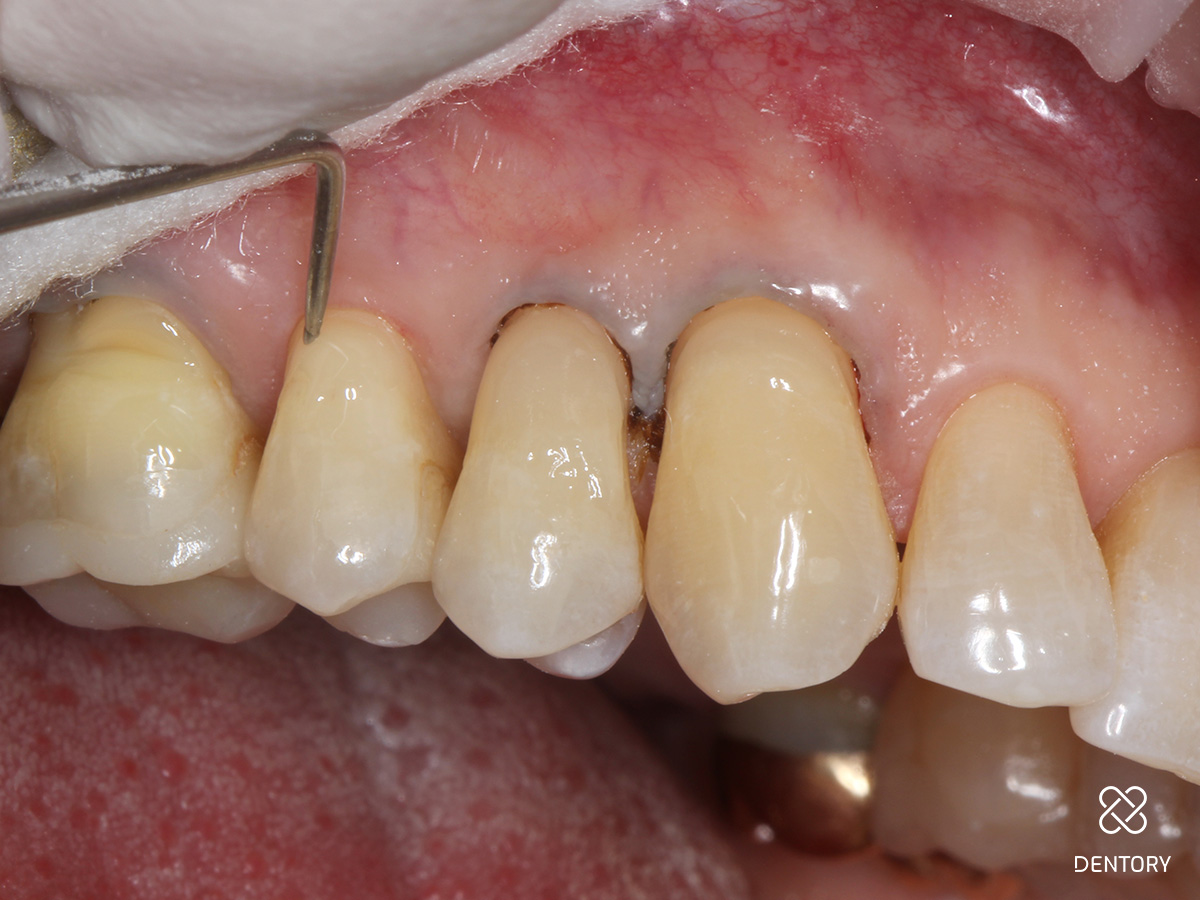

Abbildung 3

Zunächst Beläge und Biofilm sauber entfernen. Um eine Blutung des umgebenden Gewebes zu verhindern, wird ein Gingiva Schutzhalter angelegt. Das Instrument lässt sich schnell individuell anpassen und dem Zahnhals entsprechend formen. Die Gingiva wird leicht nach unten geschoben, um einen perfekten Sitz des Instrumentes zu garantieren.